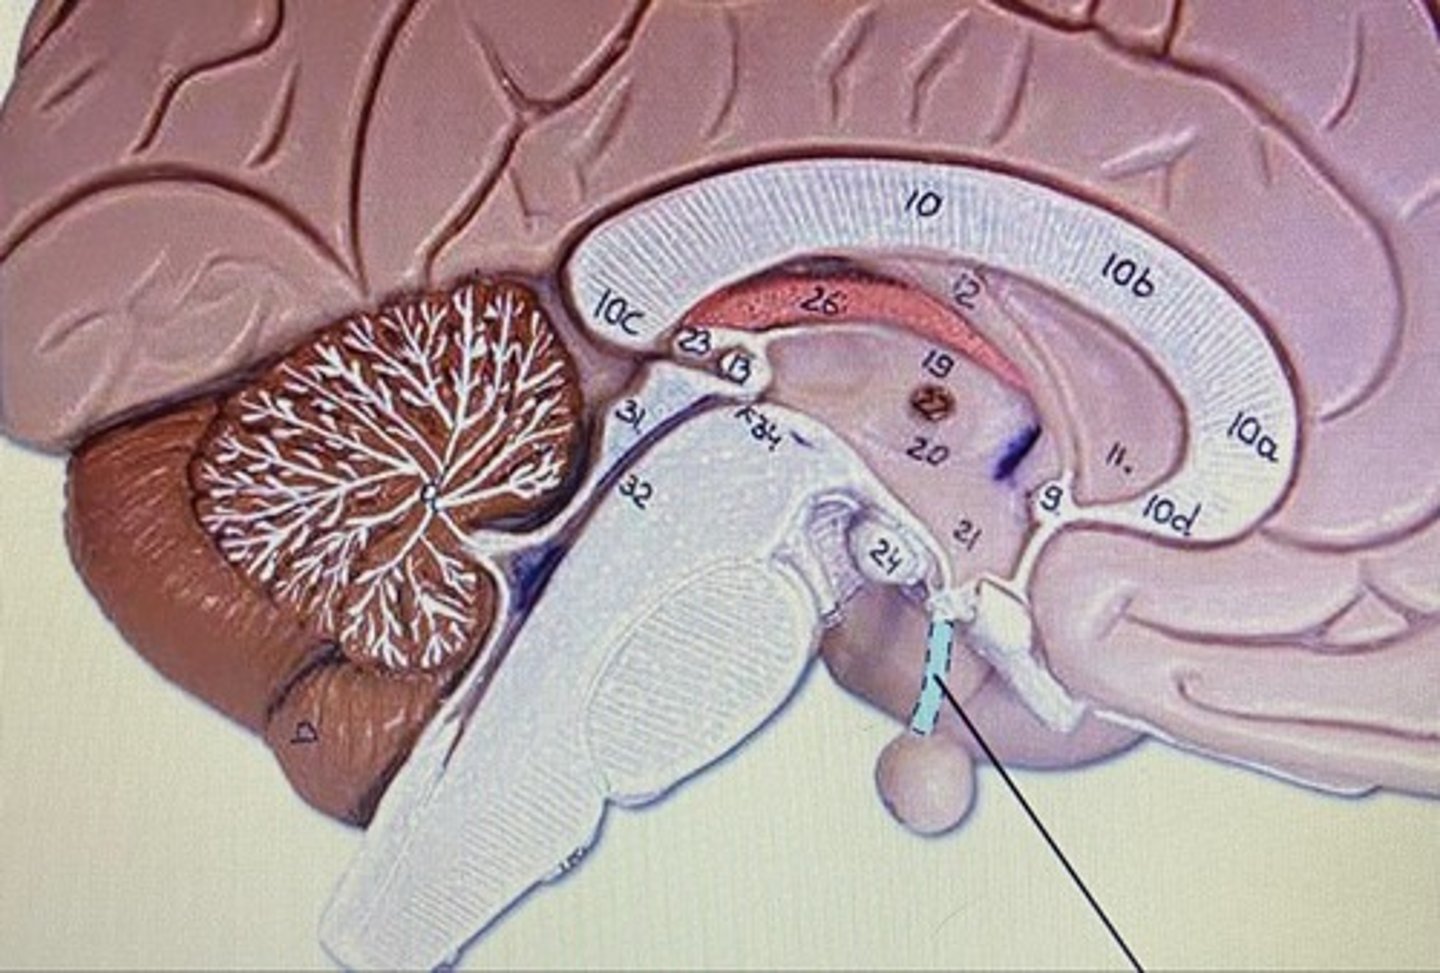

Frontal Lobe

Parietal Lobe

Temporal Lobe

Occipital Lobe

Cerebrum

Cerebellum

Arbor Vitae

Medulla Oblongata

Pineal Body/Gland

Corpus Callosum

Choroid Plexus

Fornix

Thalamus

Hypothalamus

Infundibulum

Pituitary Gland

Olfactory Bulb

Olfactory Tract

Superior Colliculus

Inferior Colliculus

Lateral Ventricle

Third Ventricle

Fourth Ventricle

Cerebral Aqueduct

Cerebrum

-conscious brain

Cerebellum

-coordinates muscles movements, muscle memory

Transverse Fissure

-separates cerebrum & cerebellum

Pons

-bridge that links medulla oblongata to thalamus

Medulla Oblongata

-houses autonomic centers

Sheep Lateral Ventricle

-produces and contains cerebrospinal fluid

Sheep Fornix

Sheep Thalamus

-gateway to cerebral cortex

Sheep Hypothalamus

-located under the thalamus on human brain

-controls pituitary gland and autonomic centers of medulla oblongata